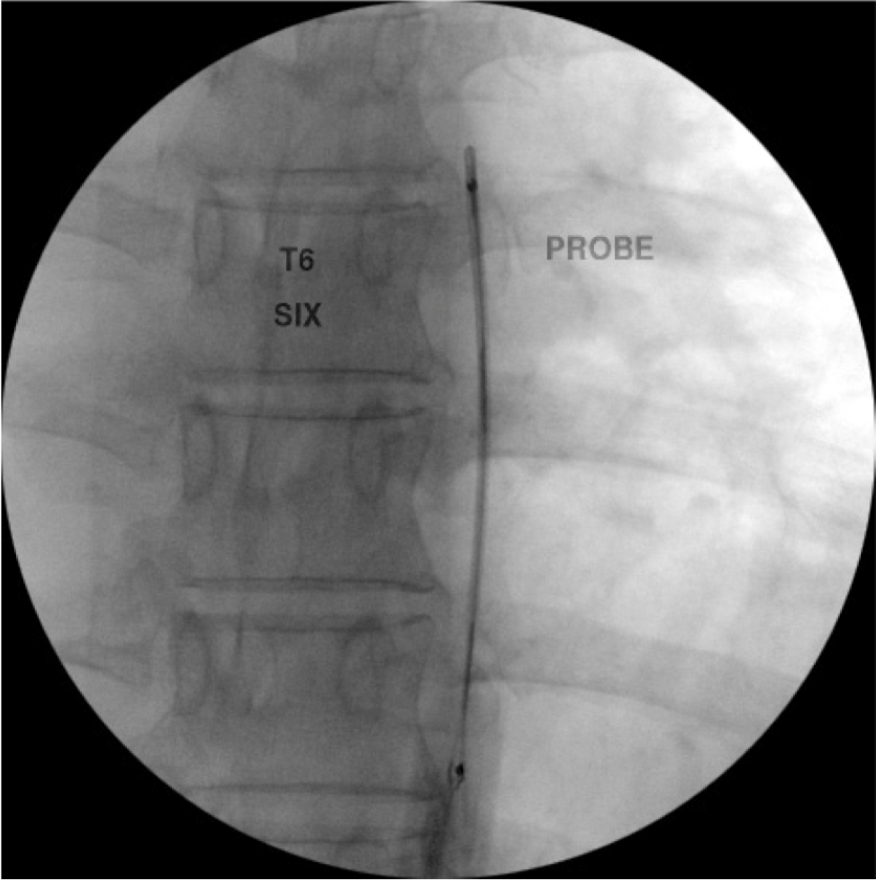

Diagnostic blocks in the thoracic region are performed by placing the needle at the superior lateral corner of the transverse process where the medial branch transverses via a posterior approach. These targets are especially true for medial branches T1-4 and T9-T10. (Figure 13). A separate injection can be made at each level. A small amount of local anesthetic (0.5 ml of 0.5% bupivacaine or 2% lidocaine) should be injected at each level. It is important to keep the needle over bone at all times to avoid damage to the pleura. It is also important to note that there is greater variability at the levels of the T5-T8. At these levels the medial branches are often found in the intertransverse spaces rather than on bone. This fact can lead to difficult when performing the procedure at these levels.

Figure 18c. Thoracic medial branch denervation procedure. The RF probe has been inserted into the RF needle and is in position just off the superior lateral edge of the T6 transverse process.

Figure 18d. Thoracic medial branch denervation procedure. Lateral view of probe in position posterior to the foramen.